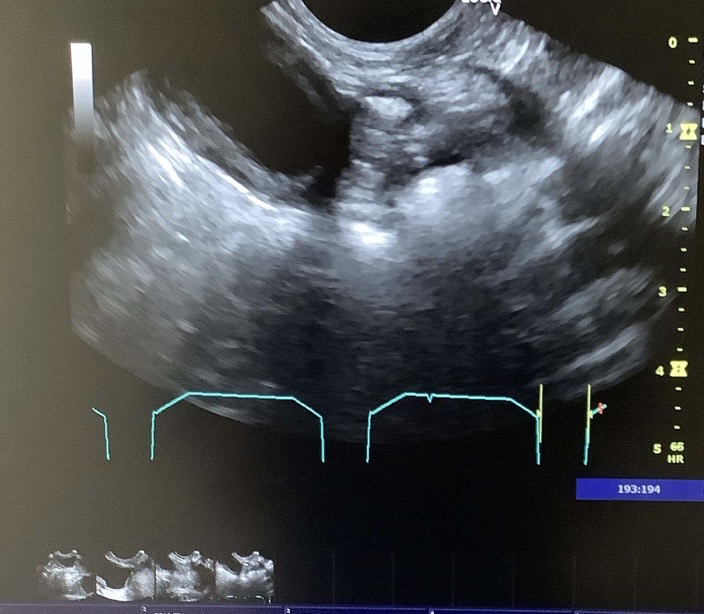

本症例(初診時高齢・小型犬)は、当初、自力での排便が困難となる「会陰ヘルニア」および「直腸憩室(腸の一部がポケット状に広がる状態)」を主訴に来院されました。複数回の手術を経てヘルニアを管理していましたが、のちに激しい嘔吐と食欲不振、極端な肝機能数値の異常(測定不能レベルの上昇)を呈し、超音波検査で肝臓に腫瘤(マス)が発見されました。

本症例は、心疾患(僧帽弁逸脱)および頸部気管虚脱という、全身麻酔において極めてリスクの高い基礎疾患を抱えていました。これらの疾患がある場合、術中の急激な血圧低下や術後の呼吸停止リスクが跳ね上がります。